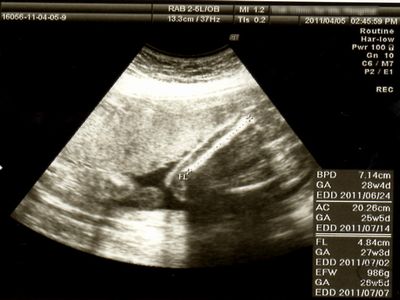

超音波写真 エコー写真 2011年4月5日 火 ソフロロジー出産 はじめての妊娠

超音波写真 エコー写真 2011年4月19日 火 ソフロロジー出産 はじめての妊娠